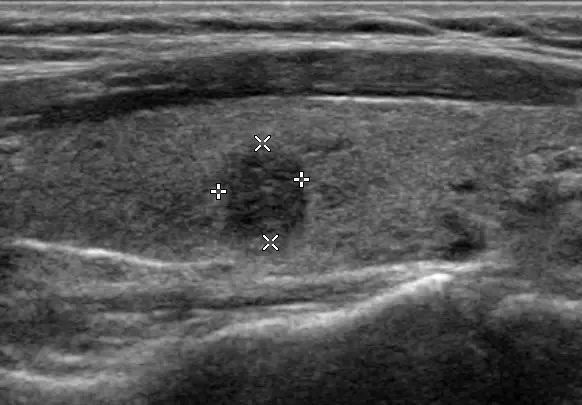

这里我们就要隆重介绍超声了,超声是鉴别甲状腺结节良恶性的首选检查方法。甲状腺结节患病率的“升高”主要就归功于健康体检制度的完善和超声等检查手段的普及。

以前检查甲状腺都用手摸,一般只能发现1cm以上的结节。现在有超声这样的神器相助,0.1cm的结节都逃不过它的法眼,所以使得长期处在深宅大院里的微小结节更容易被发现,这就也提高了甲状腺结节的检出率。

对于所有已知或怀疑存在结节的患者,都推荐进行甲状腺及其周围淋巴结的超声检查。超声对甲状腺结节的鉴别能力,甚至优于CT与磁共振。所以鉴别甲状腺结节性质的好坏超声完全就可以搞定,没必要花大价钱去做核磁共振和有伤害的造影,只有在必要时会进行细针穿刺检查。